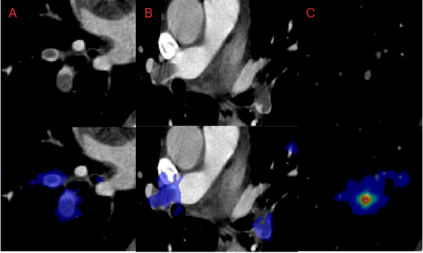

Pulmonary Embolisms (PE) represent a leading cause of cardiovascular death. While medical imaging, through computed tomographic pulmonary angiography (CTPA), represents the gold standard for PE diagnosis, it is still susceptible to misdiagnosis or significant diagnosis delays, which may be fatal for critical cases. Despite the recently demonstrated power of deep learning to bring a significant boost in performance in a wide range of medical imaging tasks, there are still very few published researches on automatic pulmonary embolism detection. Herein we introduce a deep learning based approach, which efficiently combines computer vision and deep neural networks for pulmonary embolism detection in CTPA. Our method features novel improvements along three orthogonal axes: 1) automatic detection of anatomical structures; 2) anatomical aware pretraining, and 3) a dual-hop deep neural net for PE detection. We obtain state-of-the-art results on the publicly available multicenter large-scale RSNA dataset.